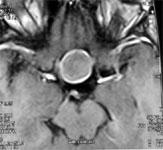

МРТ мозга должно проводиться с контрастной визуализацией. При обнаружении опухолевого образования в области гипофиза следует проконсультироваться с нейрохирургом.

Рис. 1. МРТ мозга с контрастом. Эндосупраинфраселлярная макроаденома гипофиза, сжимающая зрительные нервы и III желудочек мозга.